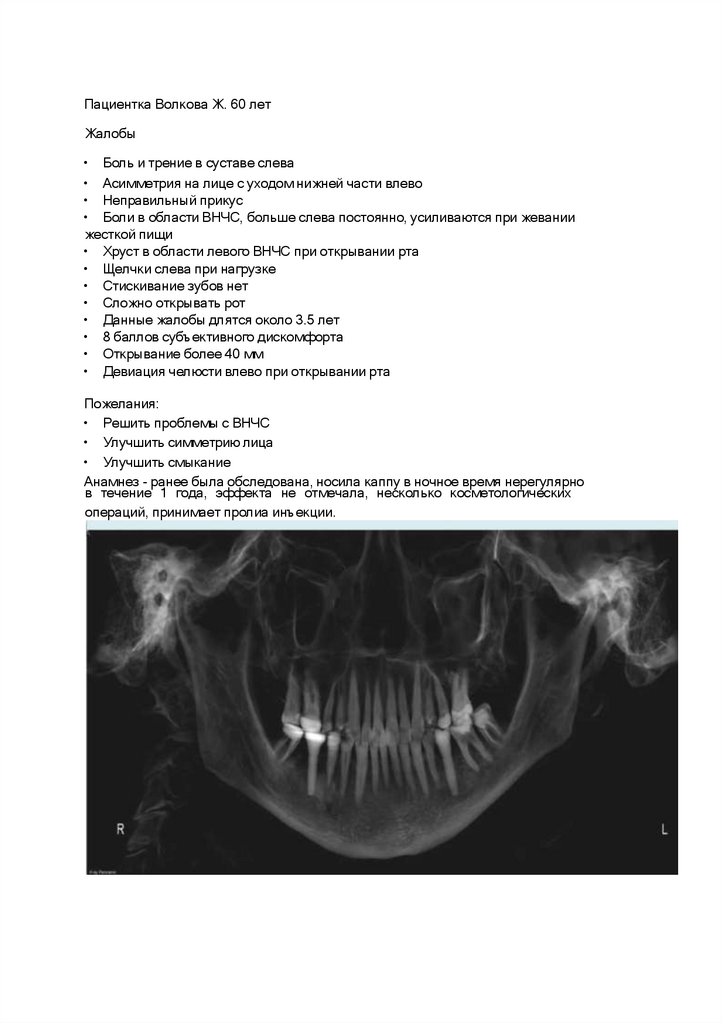

Пациентка Волкова Ж. 60 лет

Жалобы

• Боль и трение в суставе слева

• Асимметрия на лице с уходом нижней части влево

• Неправильный прикус

• Боли в области ВНЧС, больше слева постоянно, усиливаются при жевании

жесткой пищи

• Хруст в области левого ВНЧС при открывании рта

• Щелчки слева при нагрузке

• Стискивание зубов нет

• Сложно открывать рот

• Данные жалобы длятся около 3.5 лет

• 8 баллов субъективного дискомфорта

• Открывание более 40 мм

• Девиация челюсти влево при открывании рта

Пожелания:

• Решить проблемы с ВНЧС

• Улучшить симметрию лица

• Улучшить смыкание

Анамнез - ранее была обследована, носила каппу в ночное время нерегулярно

в течение 1 года, эффекта не отмечала, несколько косметологических

операций, принимает пролиа инъекции.